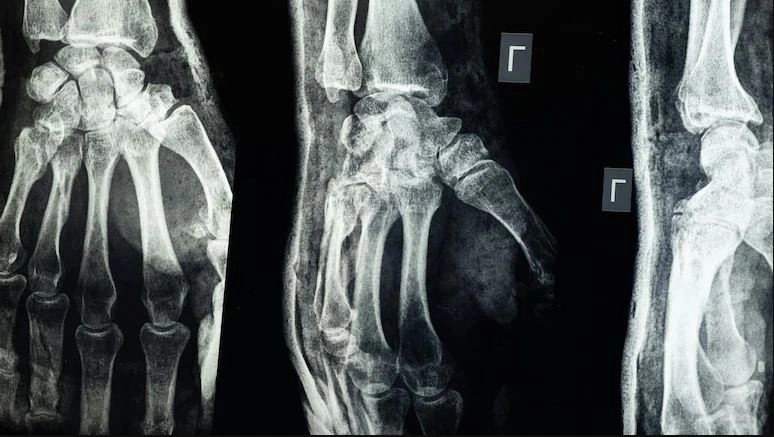

UBT NewsShkencëtarët kinezë kanë prezantuar një ngjitës të ri mjekësor të quajtur Bone-02, që riparon frakturat e eshtrave për vetëm tre minuta.

I frymëzuar nga guacat që ngjiten fort në sipërfaqe të lagështa, Bone-02 është i tretshëm nga trupi dhe zhduket brenda gjashtë muajve, duke shmangur nevojën për ndërhyrje të dytë kirurgjikale.

Ky ngjitës është testuar me sukses në mbi 150 pacientë, duke treguar forcë të madhe, ngjitje të shpejtë dhe tolerancë të lartë nga trupi.

Ai funksionon edhe në mjedise me shumë gjak dhe mund të zëvendësojë implantet tradicionale si vidat apo plakat metalike.

Bone-02 pritet të përshpejtojë shërimin, të ulë rrezikun e infeksioneve, dhe të ketë përdorim të gjerë në kirurgji, mjekësi emergjente, luftime apo katastrofa natyrore.

Ekspertët e quajnë një ndryshim të madh në trajtimin e frakturave. /A.Z/UBT News/